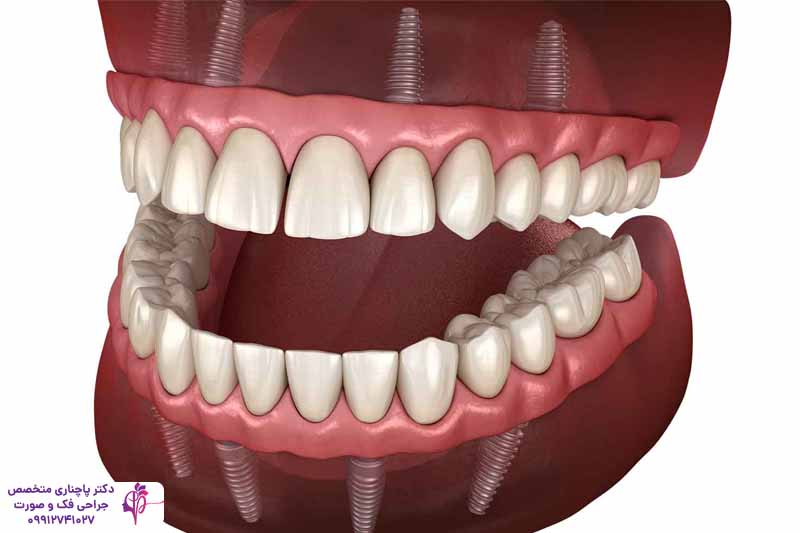

اوردنچر بر پایه ایمپلنت دندان یکی از هوشمندانهترین و محبوبترین راهحلهای درمانی برای کسانی است که تمام یا بیشتر دندانهای یک فک یا هر دو فک خود را از دست دادهاند. اوردنچر بر پایه ایمپلنت، پروتزی متحرک است که با استفاده از پایههای فلزی کوچک یا همان پایههای تیتانیومی ایمپلنت دندان در استخوان فک تثبیت میشود. این پروتز را میتوانید مثل دندان مصنوعی معمولی شبها دربیاورید و تمیز کنید، اما در طول روز محکم روی جای خود مینشیند و موقع غذا خوردن یا حرف زدن تکان نمیخورد. برای انجام اوردنچر بر پایه ایمپلنت دندان فقط دو تا شش پایه تیتانیومی نیاز دارید. با این روش هم به عملکرد بهتر دهان و دندان کمک میکنید و هم جلوی تحلیل رفتن استخوان فک را میگیرید.

اوردنچر بر پایه ایمپلنت دندان، نسخه پیشرفتهتری از اوردنچر سنتی است که در آن به جای دندانهای طبیعی از ایمپلنتهای تیتانیومی به عنوان پایه استفاده میشود. ایمپلنتها پیچهای کوچکی هستند که در استخوان فک کاشته میشوند و مانند ریشههای طبیعی دندان عمل میکنند. بعد از کاشت پایهها پروتز اوردنچر روی آنها نصب میشود.

این روش برای بیمارانی که همه یا تعداد زیادی از دندانهای یک فک را از دست دادهاند ایدهآل است. ایمپلنتها با ادغام شدن با استخوان فک از تحلیل رفتن آن جلوگیری میکنند. در فک پایین معمولا دو ایمپلنت کافی است ولی برای فک بالا گاهی 4 تا 6 پایه استفاده میکنند. بعد از کاشت پایهها 3 تا 6 ماه طول میکشد تا پایه با استخوان ادغام شود و بعد از آن پروتزی که با دقت در آزمایشگاه ساخته شده روی آن نصب میشود. این ترکیب پایه و پروتز اوردنچر را به یک گزینه عالی تبدیل کرده که هم محکم است و هم بیمار میتواند مدلهای متحرک را برای تمیز کردن جدا کند.